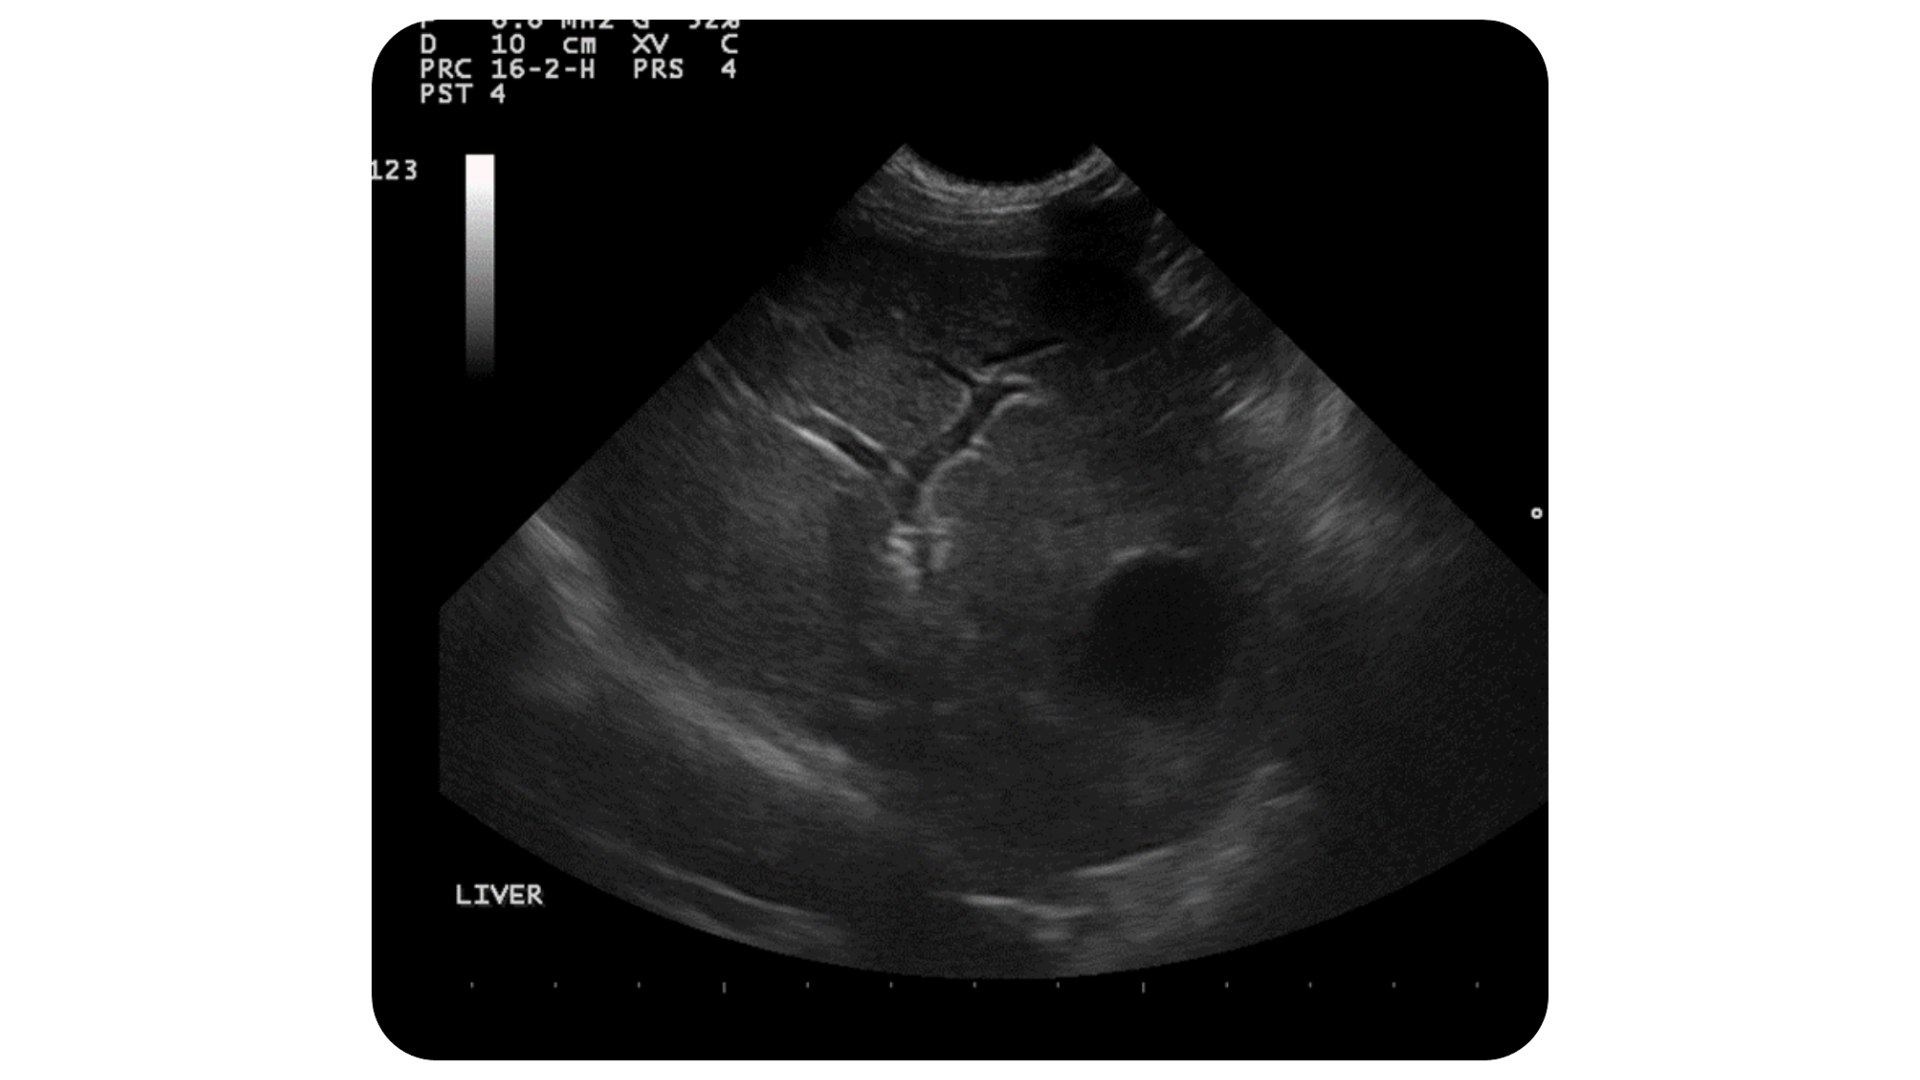

In this image we can see the near field (closest to the probe at the top of the image) is crisp and clear because we are using a high frequency. However, that high frequency is not penetrating well to the bottom of our image, leaving the liver looking blurry and unclear.